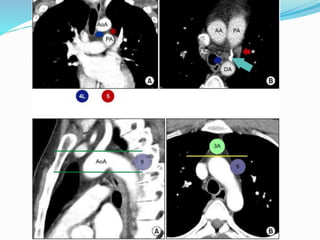

•Stage T4

tumors.

•T4 tumor due

to invasion of

pulmonary

artery (arrow,

a),

•Descending

aorta (arrow, b),

•Vertebral body

(arrow, c),

•Superior vena

cava with

thrombus

(arrow, d)

•Stage T4 tumors. •T4 tumordue to invasion of pulmonary artery (arrow, a), •Descending aorta (arrow, b), •Vertebral body (arrow, c), •Superior vena cava with thrombus (arrow, d)